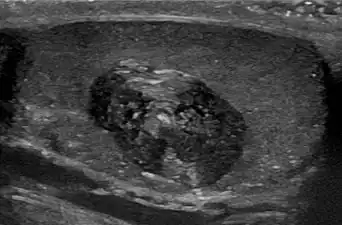

Les kystes épidermiques sont généralement diagnostiqués lorsqu'une personne remarque une bosse sur la peau et consulte un médecin. Le diagnostic définitif est posé après exérèse, par un médecin pathologiste sur la base de l'aspect microscopique d'une lésion kystique bordée d'un épithélium malpighien contenant de la kératine lamellaire[5]. Ils peuvent également être observés sous forme de lésions isointenses en IRM ou d'hyperintensités en FLAIR.